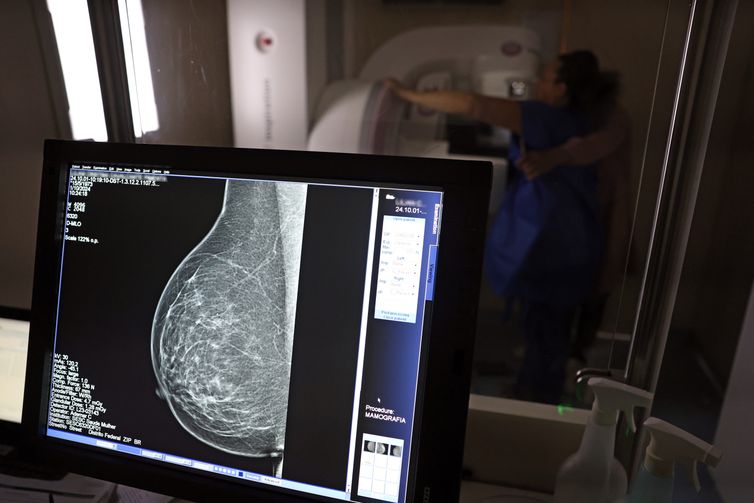

Falta de acesso a mamógrafos limita prevenção do câncer de mama

Atlas da Radiologia mostra que país tem baixa cobertura de mamografias, 24%. O ideal, recomendado pela OMS, é de 70%.

© José Cruz/Agência Brasil

No mês de conscientização sobre o câncer de mama, um relatório destaca a importância de acesso igualitário ao rastreamento e tratamento da doença. Segundo o Atlas da Radiologia no Brasil, do Colégio Brasileiro de Radiologia e Diagnóstico por Imagem (CBR), o acesso aos mamógrafos ainda é um desafio.

O país tem 6.826 equipamentos registrados, sendo 96% em funcionamento. Metade deles está disponível no Sistema Único de Saúde (SUS), responsável por atender 75% da população. Isso equivale a 2,13 mamógrafos por 100 mil habitantes dependentes do SUS.

Na saúde suplementar, que cobre 25% da população, o cenário é mais favorável: 6,54 aparelhos por 100 mil beneficiárias, quase o triplo da rede pública. O Acre exemplifica essa disparidade — são 35,38 mamógrafos por 100 mil habitantes na rede privada, contra 0,84 no SUS.

Há disparidades regionais. Roraima tem a menor proporção (1,53 por 100 mil), seguida do Ceará (2,23) e Pará (2,25). A Paraíba lidera o ranking (4,32), à frente do Distrito Federal (4,26) e do Rio de Janeiro (3,93).

O Brasil tem uma cobertura muito baixa de mamografias: 24%. O ideal recomendado pela Organização Mundial da Saúde é de 70%. Mesmo em lugares como o estado de São Paulo, que tem a maior concentração de mamógrafos do país, a taxa gira em torno de 26%.

Em setembro, o Ministério da Saúde ampliou as diretrizes de rastreamento, recomendando que mulheres entre 40 e 49 anos realizem mamografias, mesmo sem sintomas. De acordo com o Instituto Nacional do Câncer (Imca), mais de 73 mil mulheres recebem o diagnóstico de câncer de mama anualmente no Brasil.